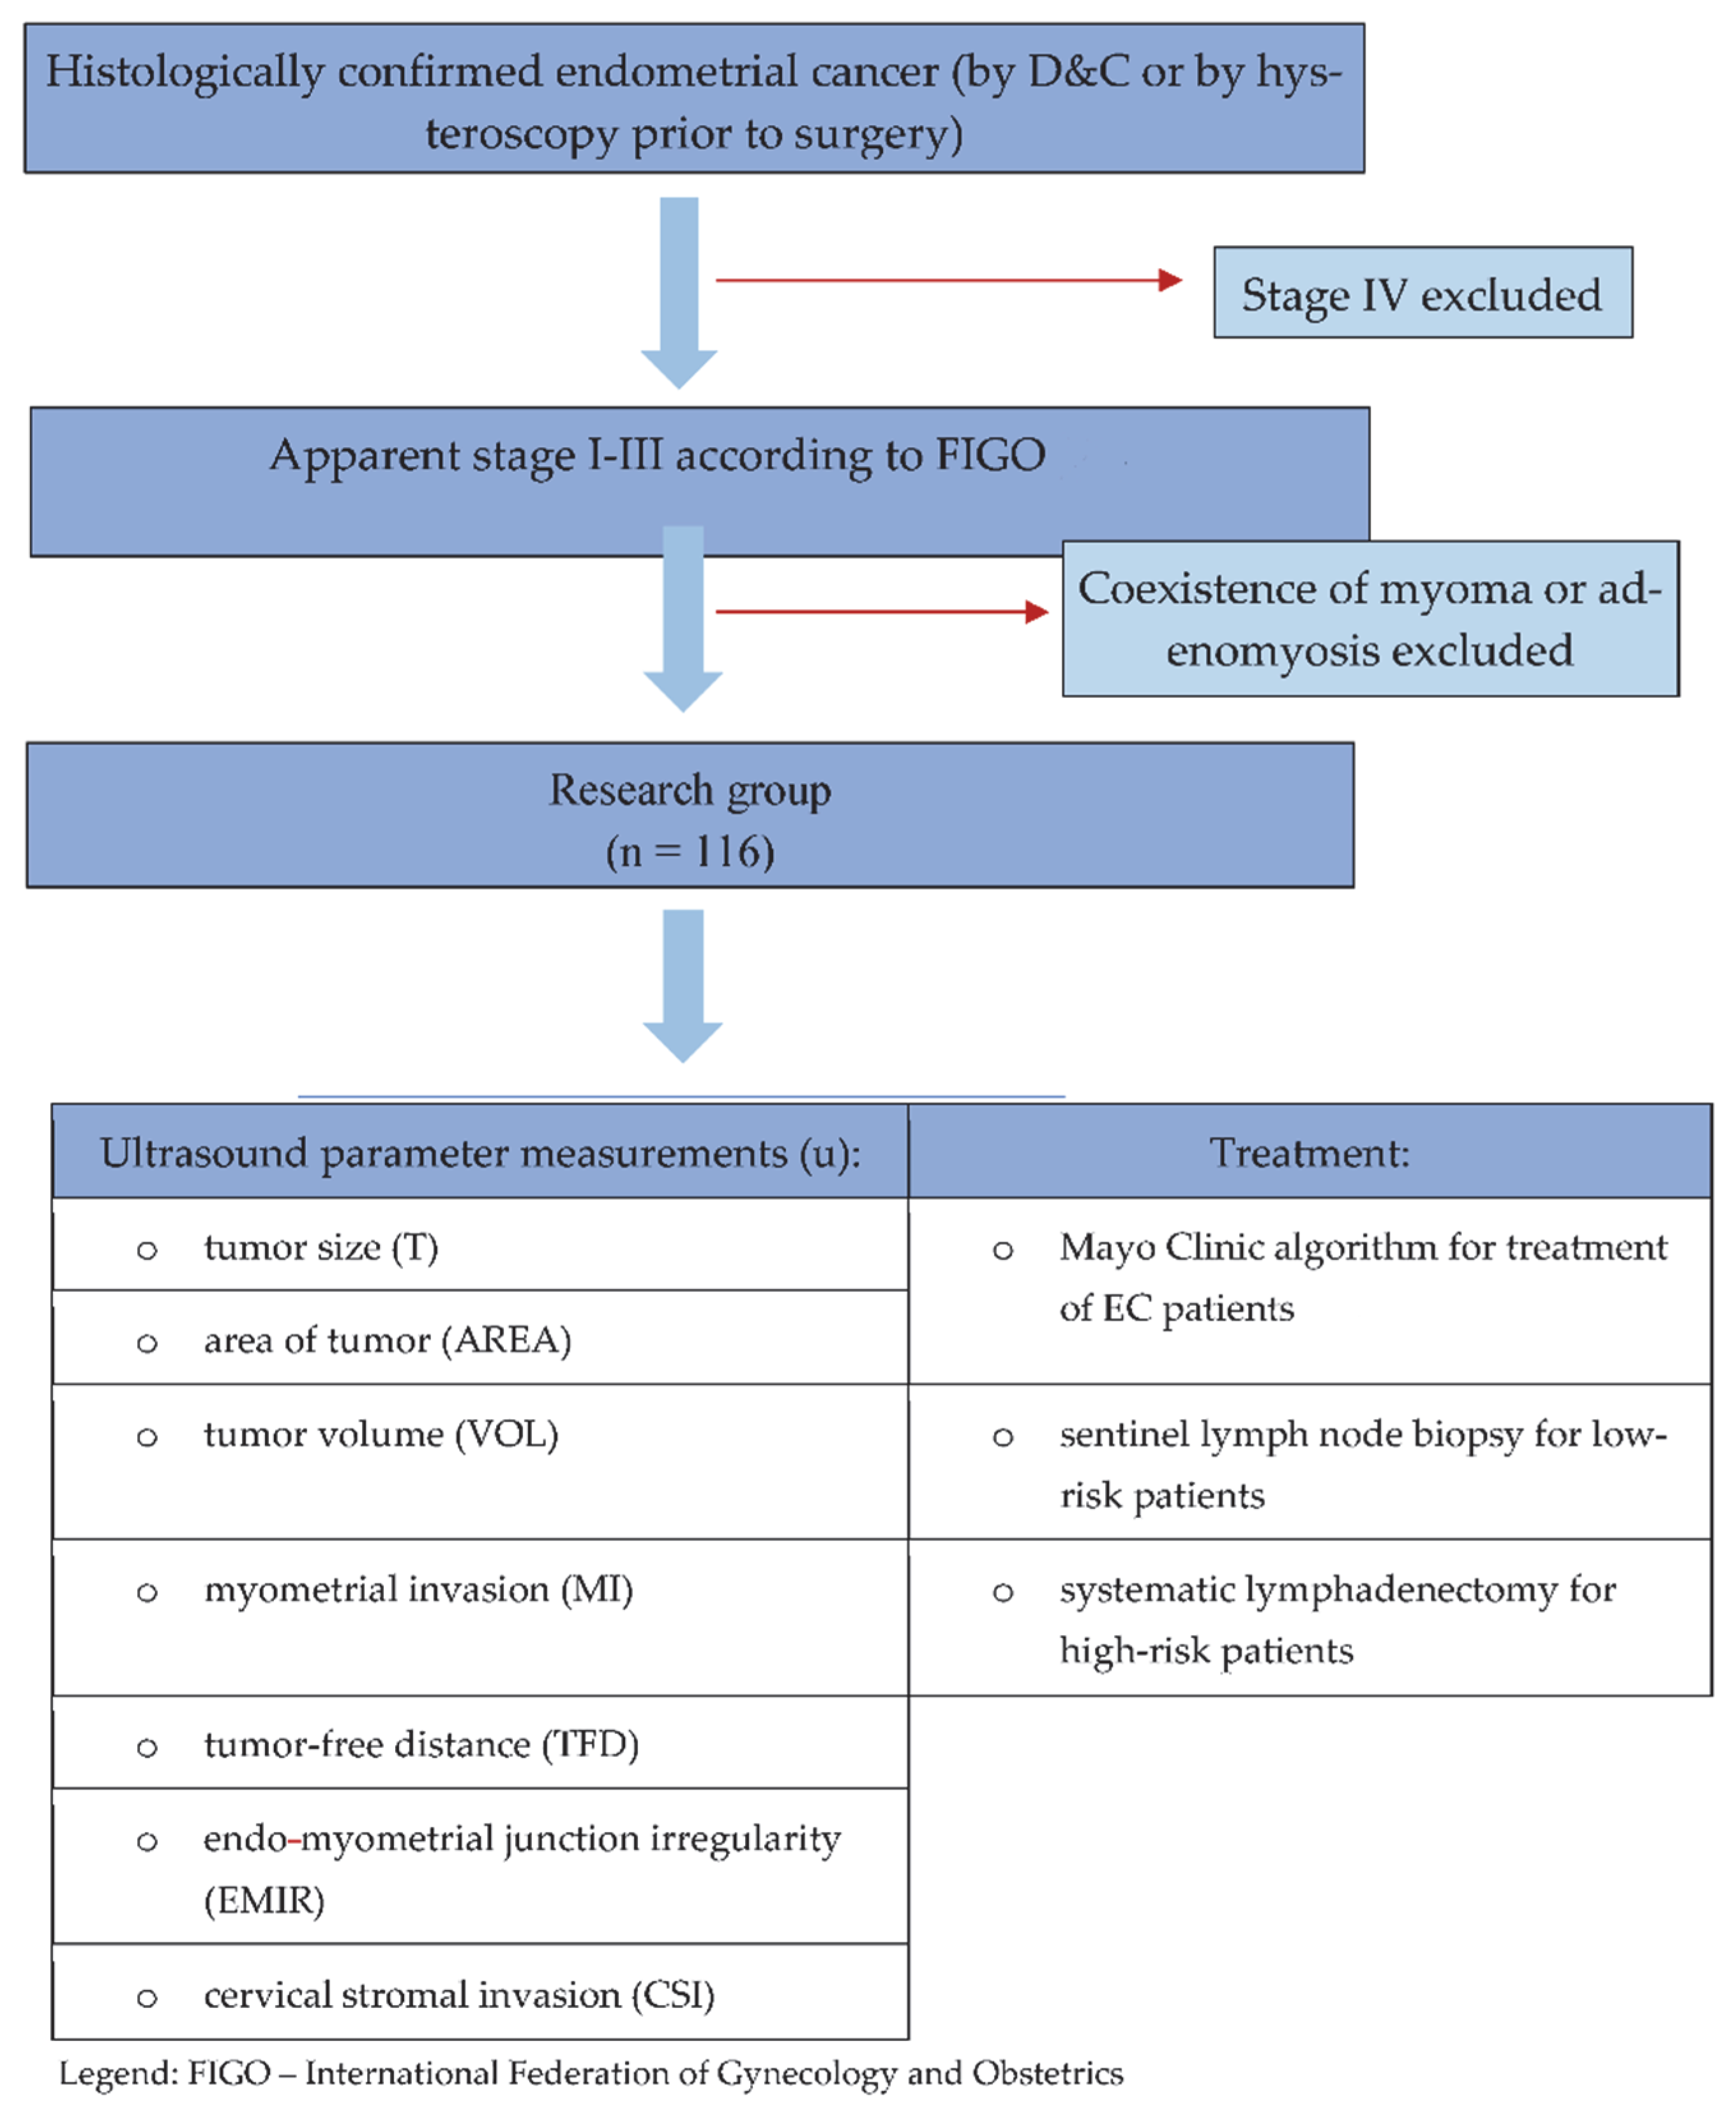

2. Materials and Methods

2.1. Study Design and Participants

2.2. Ultrasound Examination

2.3. Surgery, Including Lymph Nodes Procedure

2.4. Histopathology

2.5. Statistical Analysis